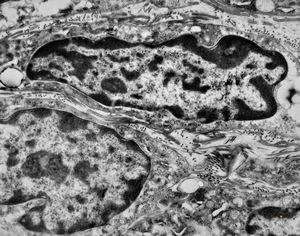

F,41y. | synovial metaplasia - capsule of implantate